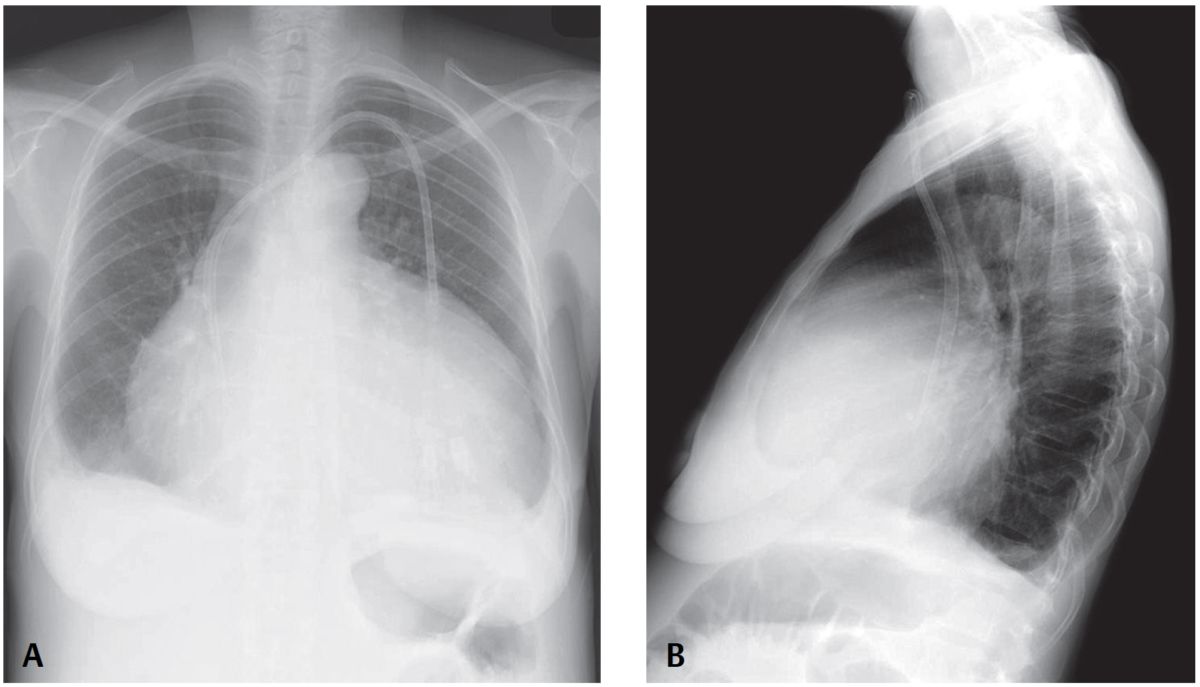

PA chest X-ray reveals an enlarged cardiomediastinal silhouette with an increase in the transverse diameter but no increase in its height, and straightening of the upper mediastinal borders, creating a globular or water bottle morphology (water bottle sign). The vascular clarity is slightly diminished and bilateral pleural effusions are present, right greater than left.

Lateral exam also shows globular enlargement of the cardiomediastinal silhouette and separation of the outer retrosternal and inner epicardial fat lines—fat pad or Oreo cookie sign).

- Increased transverse dimension of cardiomediastinal silhouette (water bottle sign) (80% specific; 46% sensitive)

- Separation of retrosternal and epicardial fat stripe >2 mm (fat pad or Oreo® cookie sign) (94% specific; 12% sensitive); seen best with moderate-large pericardial effusions